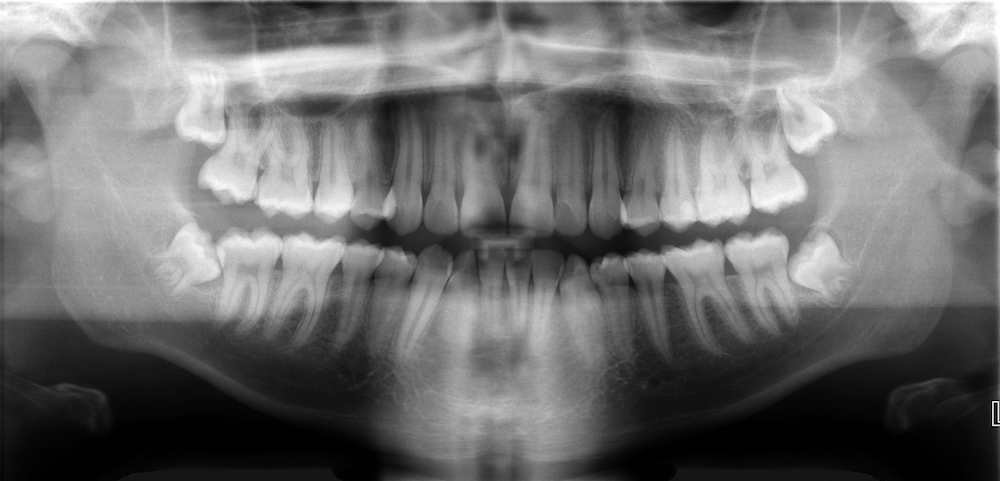

Digital X-ray

Modern technology has changed the way we take dental x-rays at Ankura Dental clinic. Advanced Digital radiology technology allows us to use computerized sensors rather than film to capture images of your teeth in order to reduce the amount of radiation exposed.